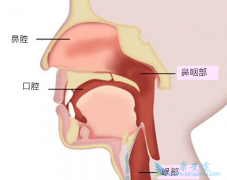

鼻咽癌 是一种发生于鼻咽腔顶部和侧壁的恶性肿瘤。鼻咽癌的发生会造成患者涕血和鼻出血的情况发生,并且鼻咽癌的发生还会导致患者耳部和头部持续性的疼痛症状。康安途医学博士提醒患者,发生鼻咽癌之后除了进行常规的治疗手段之外,在生活当中对于鼻咽 ...